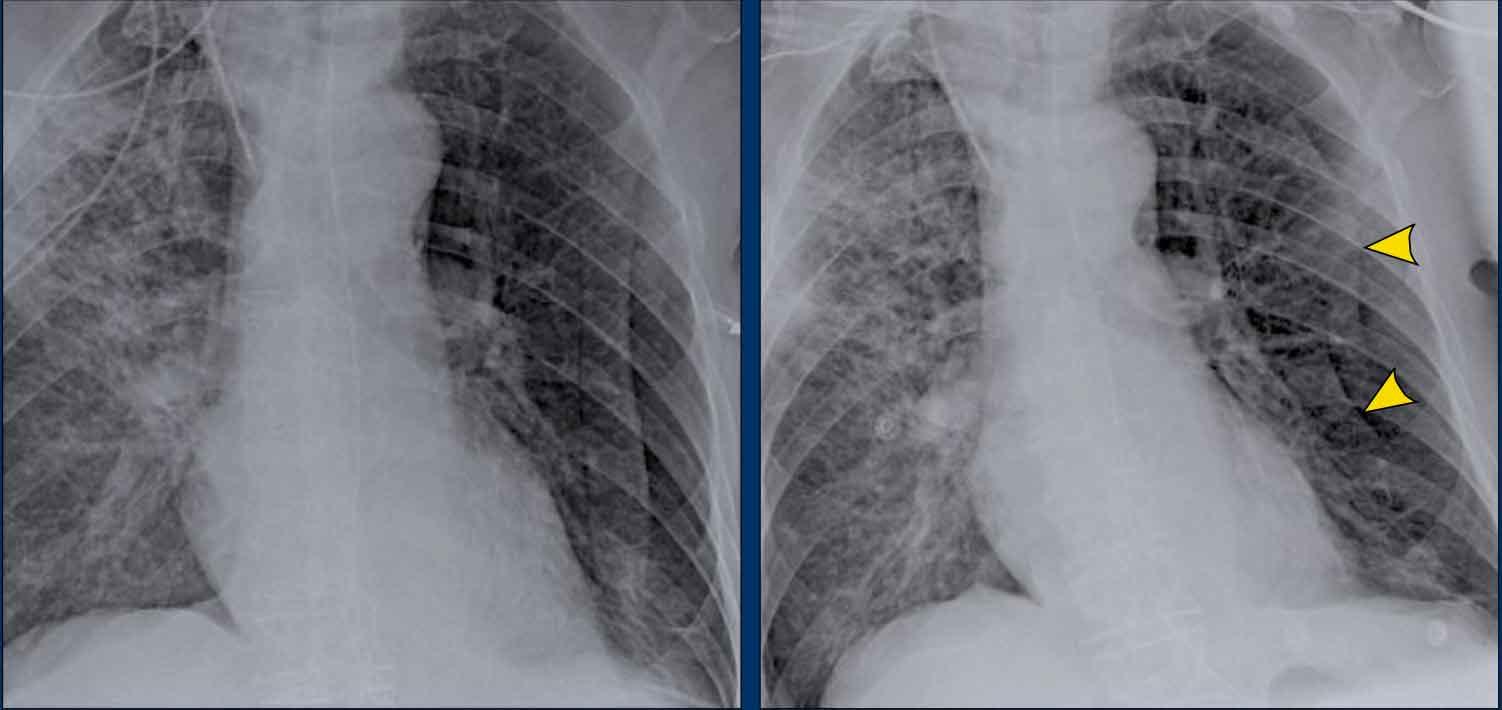

Ca lâm sàng 2 – Bệnh phổi dạng nang kèm tràn khí tràn dịch màng phổi

- X-quang ngực

- Lệch trung thất sang trái

- Mức khí-dịch (tràn khí tràn dịch màng phổi) (mũi tên đen)

- Dính thùy trên vào thành ngực. Có thể bệnh nhân này đã được điều trị tràn khí màng phổi trước đó.

- Nang phổi ở thùy trên phổi phải (đầu mũi tên vàng)

Kết luận

Đây là trường hợp bệnh nhân nữ mắc bệnh phổi dạng nang, có thể đã từng bị tràn khí màng phổi nhiều lần trước đó.

Chẩn đoán có khả năng nhất là u cơ trơn bạch mạch phổi (LAM), một bệnh phổi dạng nang hiếm gặp đặc trưng bởi sự tăng sinh tế bào cơ trơn, dẫn đến tắc nghẽn đường thở, hình thành nang phổi và tràn khí màng phổi tái phát.

LAM có thể xảy ra tự phát hoặc liên quan đến bệnh xơ cứng củ (TSC).